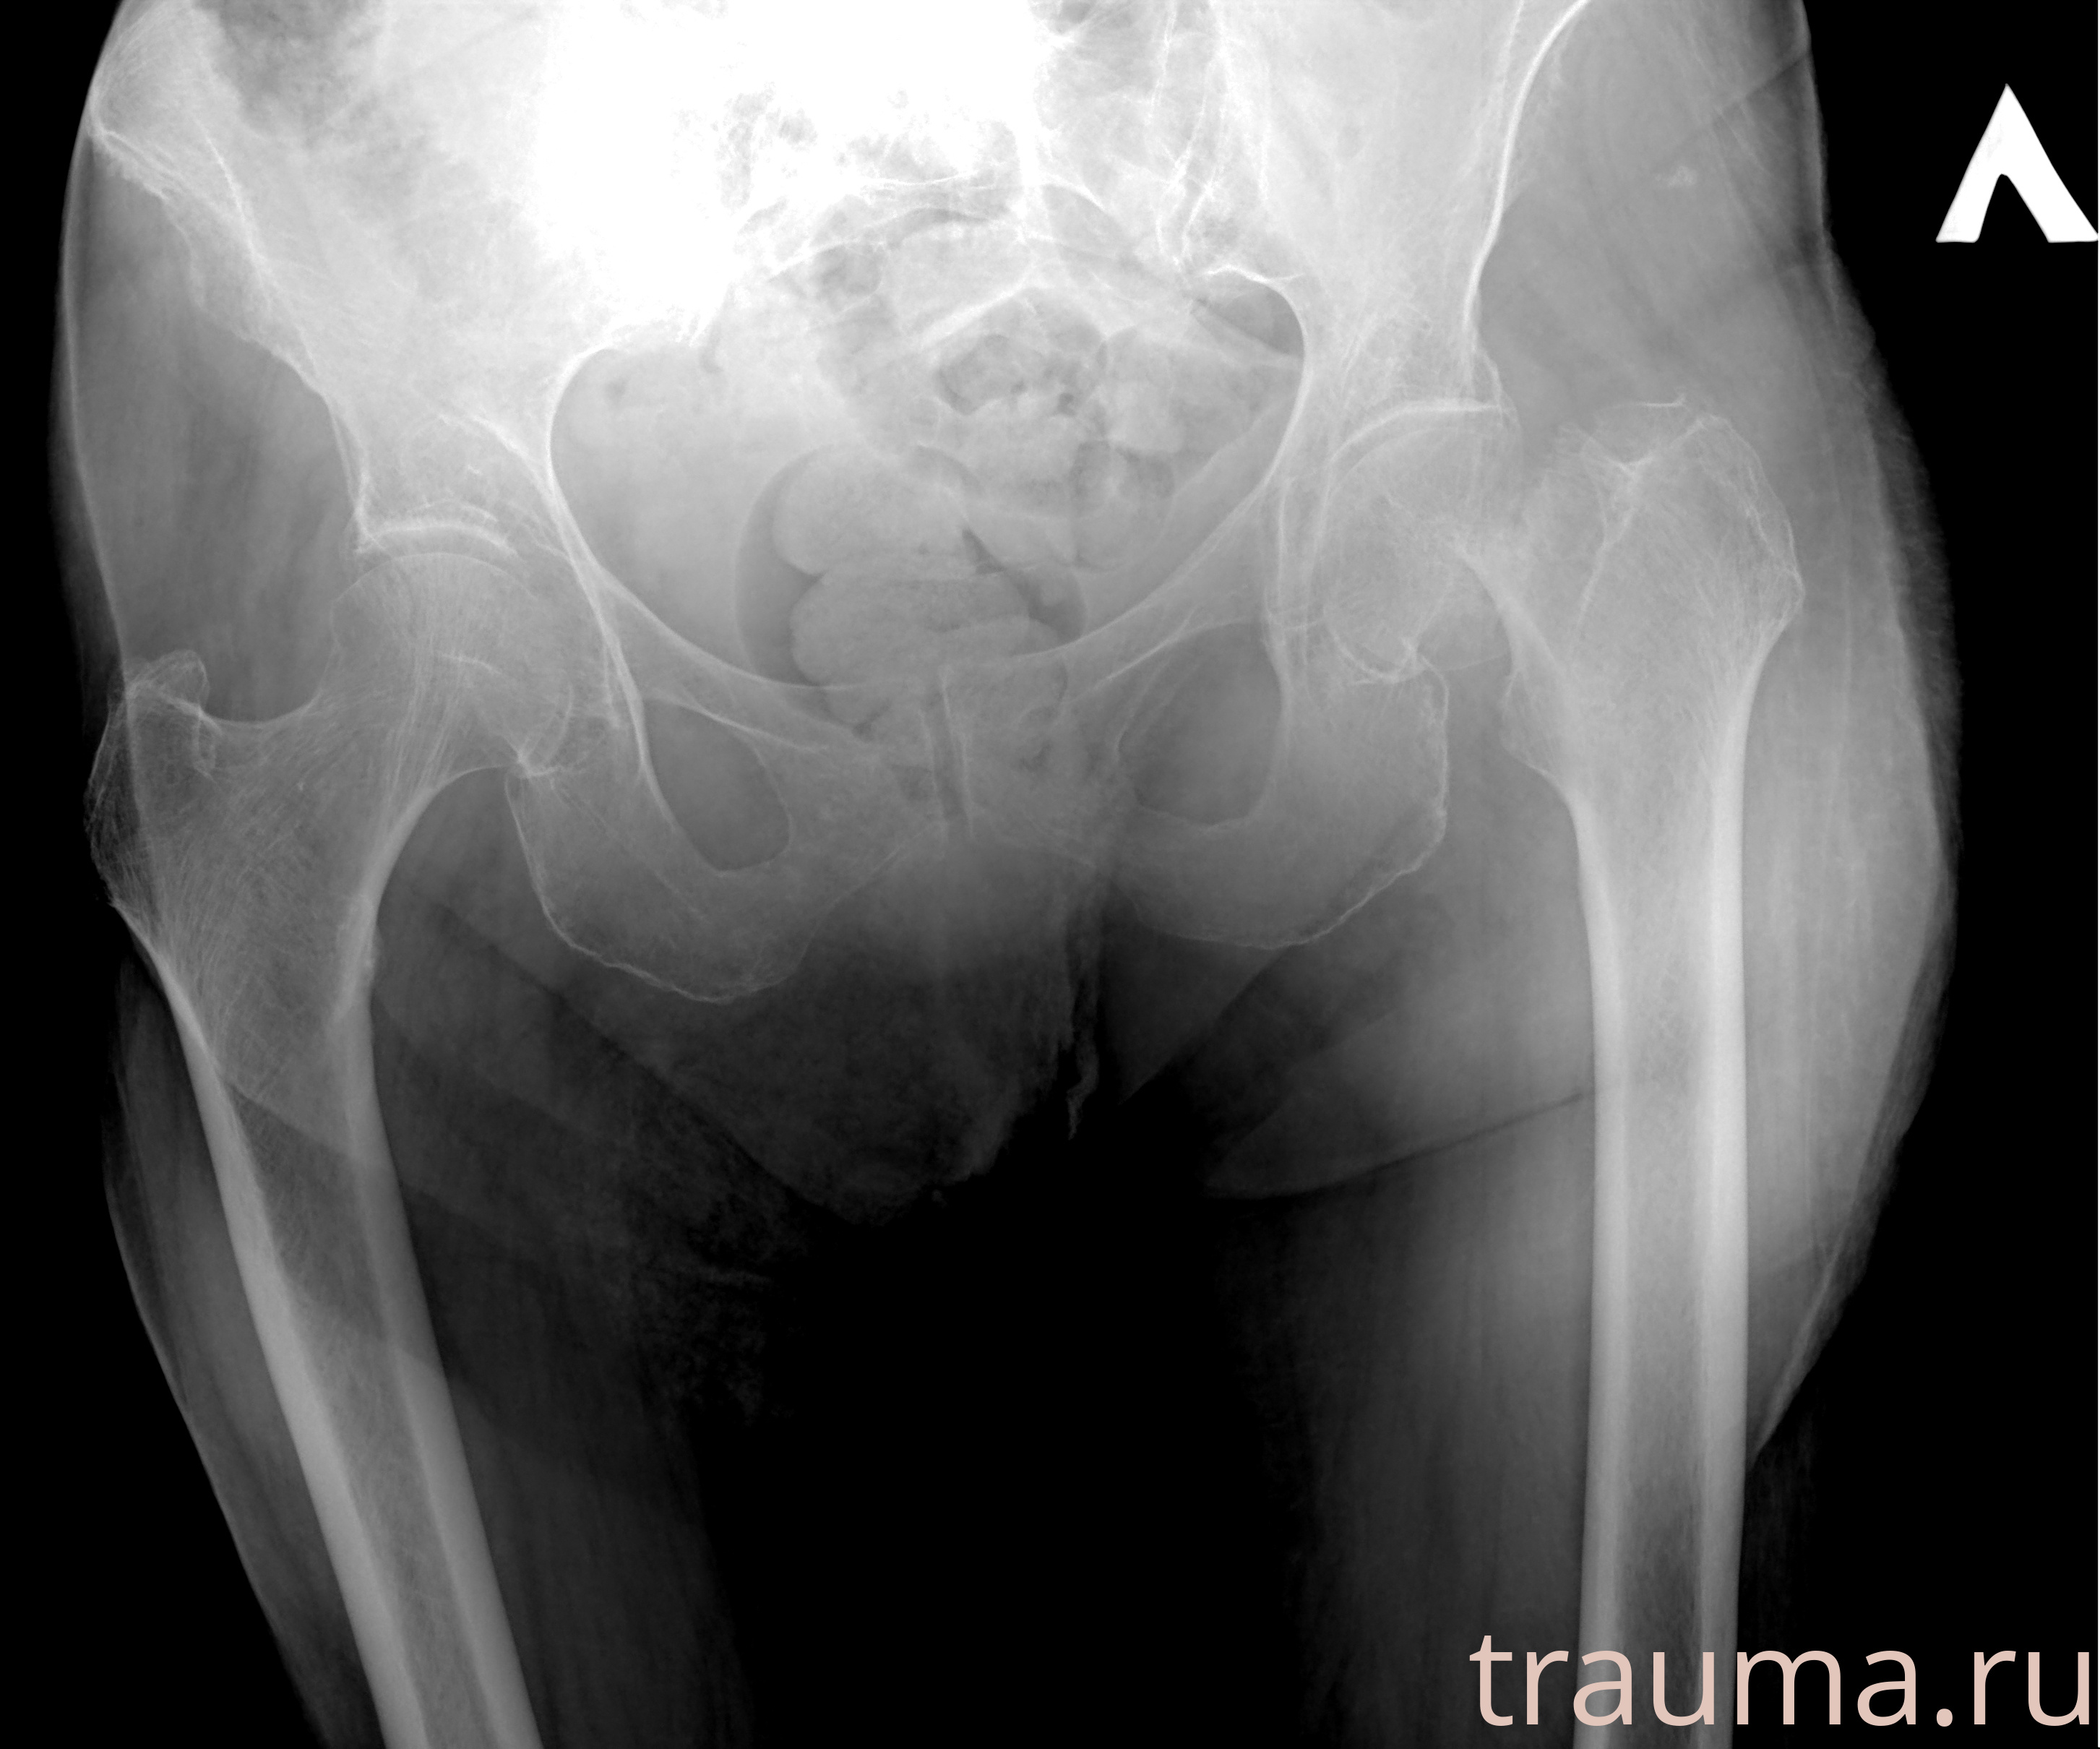

Рентген на дому: по вашему адресу приезжает врач-рентгенолог, травматолог-ортопед с мобильным рентгеновским аппаратом, проводит диагностику травмы или заболевания, делает необходимые рентгенограммы, дает рекомендации по дальнейшему лечению. Получить качественные снимки в домашних условиях возможно благодаря уникальной методике, разработанной МосРентген Центром для института  Склифосовского